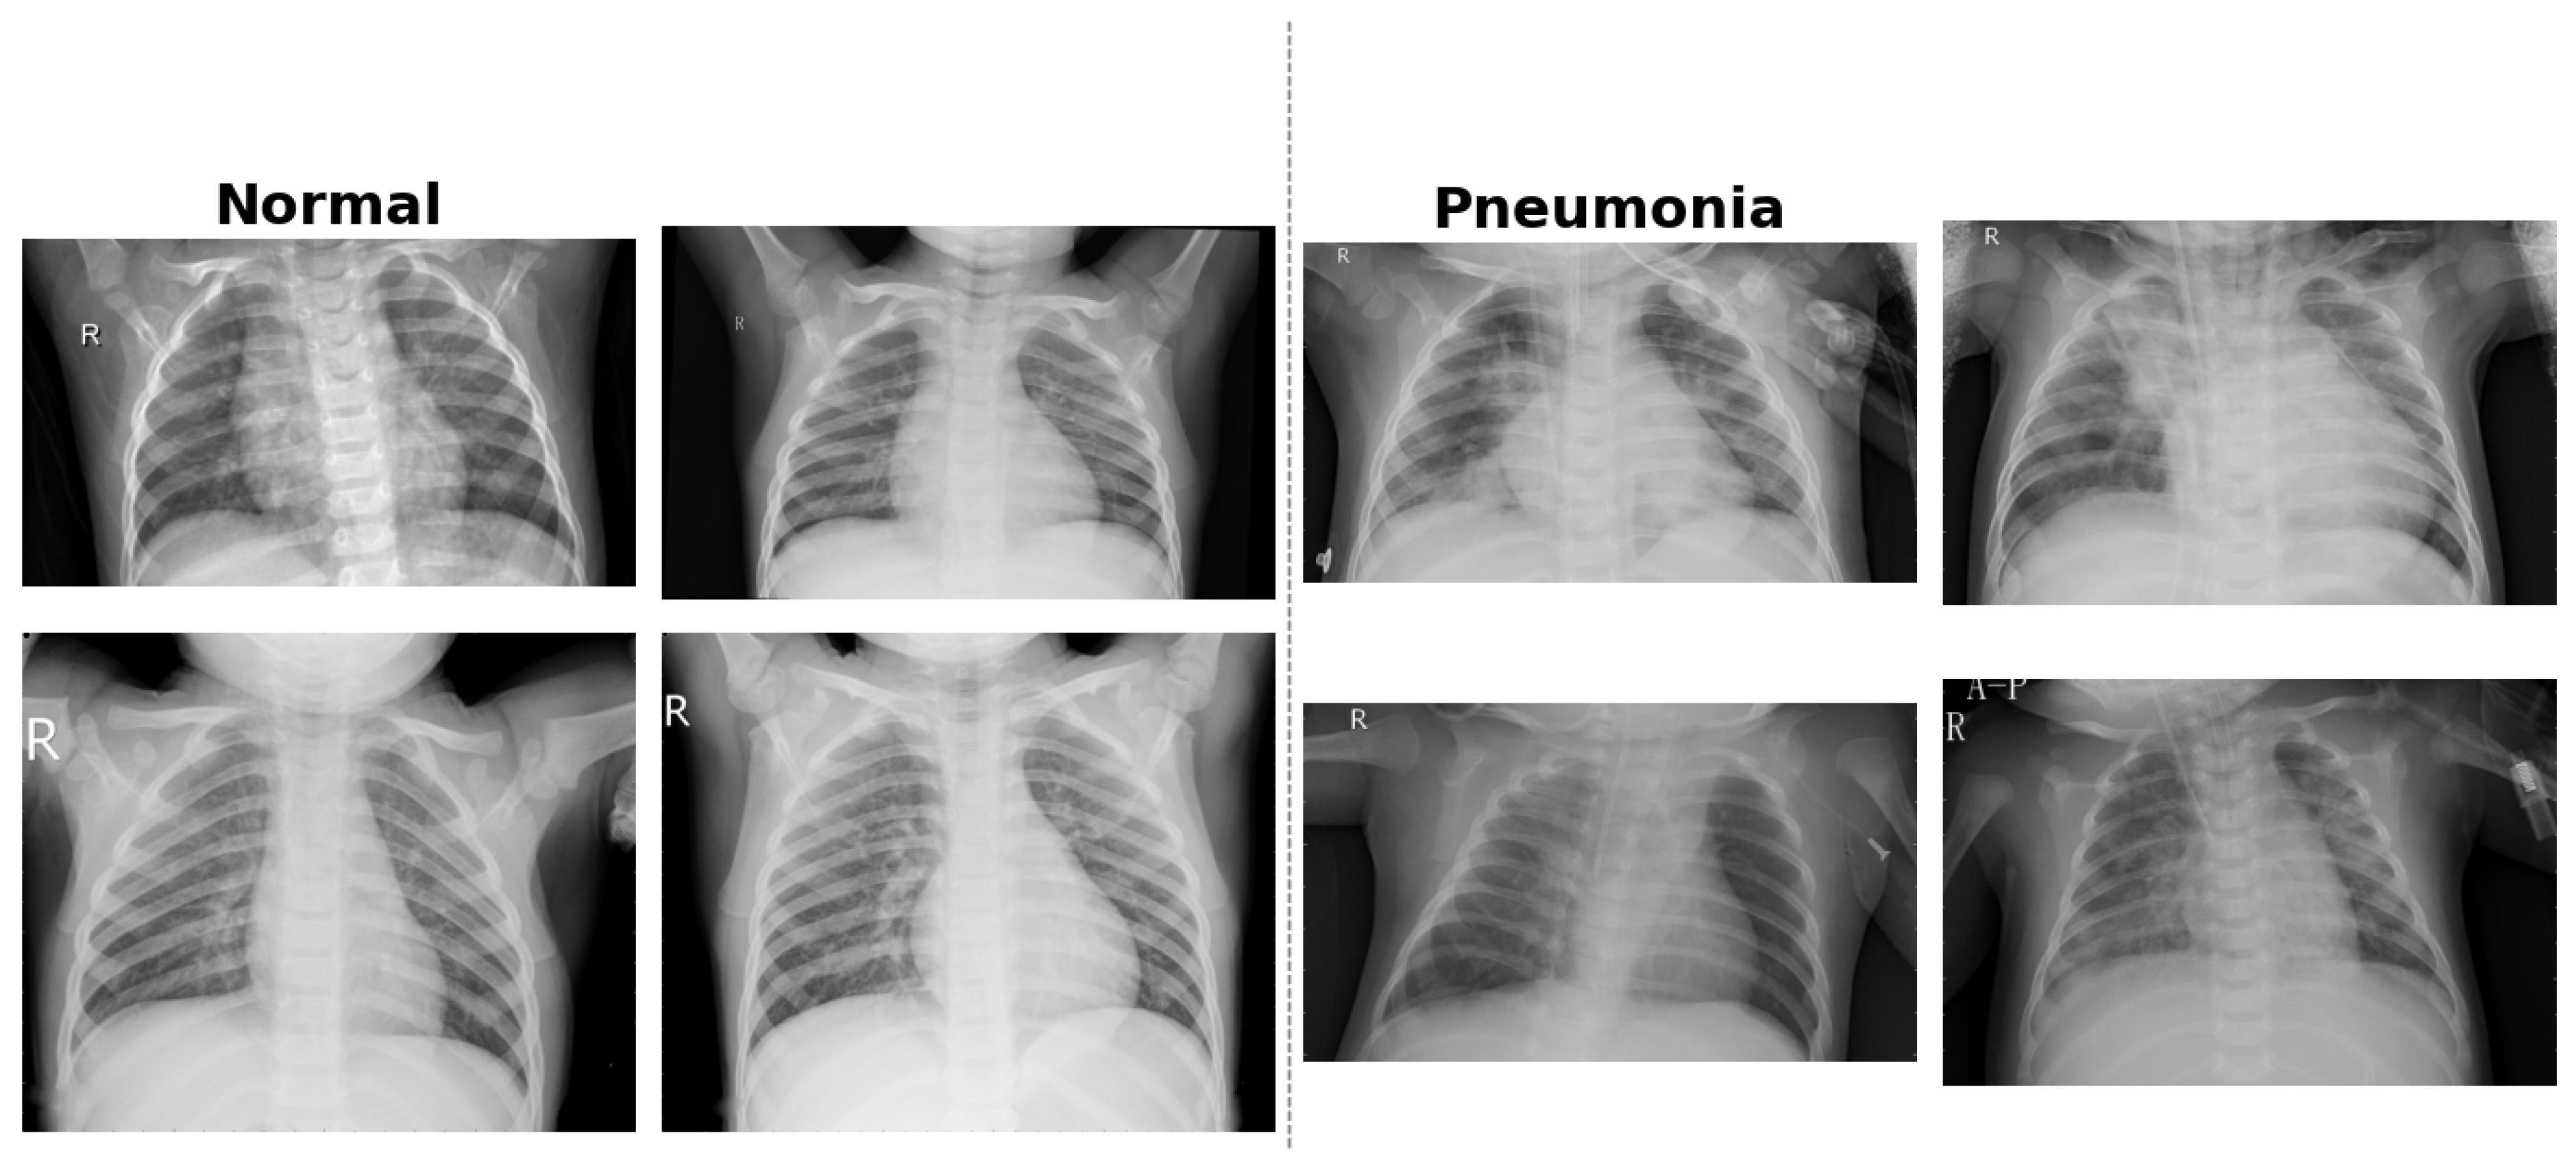

The dataset used in this study is the publicly available CXR Images (Pneumonia) dataset, originally introduced as part of a clinical study published in the journal Cell [32]. It contains 5863 anterior-posterior (AP) chest X-ray images of pediatric patients aged 1–5 years. The data were collected at the Guangzhou Women and Children’s Medical Center in China as part of routine clinical care. All radiographs underwent an initial quality screening, and low-quality or unreadable scans were excluded. Diagnostic labels—classified as either Normal or Pneumonia (bacterial or viral)—were assigned based on expert evaluation. Each image was independently reviewed by two certified radiologists, and to ensure diagnostic accuracy, a third specialist evaluated a subset of images to reduce annotation errors

The dataset is organized into three predefined folders: training, validation, and testing. These subsets are balanced across the two classes, facilitating supervised learning and consistent performance evaluation. The images are in JPEG format and exhibit sufficient resolution for feature extraction via CNNs. The dataset is available under a Creative Commons (CC BY 4.0) license and can be accessed through Mendeley Data [33]. Figure 6 provides example CXR scans illustrating the visual differences between normal lungs and those affected by bacterial and viral pneumonia.

Figure 6.

Examples of pediatric CXR images: (left) normal lung, (middle) bacterial pneumonia with localized consolidation, and (right) viral pneumonia with bilateral interstitial patterns. The letter “R” on the radiographs indicates the right side of the patient, following standard radiological convention.